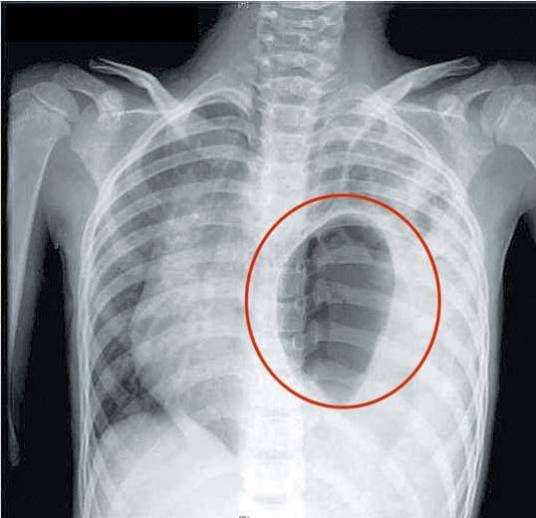

(8)渗出性胸膜炎:左下胸和左上腹明显疼痛,左侧胸呼吸音减弱,叩诊浊音,X检查示:左侧胸腔积液,但胸部仔细听诊可闻及肠鸣,钡餐检查可发现胸内有充钡的肠攀影。

(9)左侧气胸:心脏右移、心音远弱,左上胸叩诊呈鼓音,下胸叩诊呈浊音, 语颤减弱,呼吸音减弱,胸透为左胸腔有气液征,根据胸腔内有气液征象,可与气胸进行鉴别。叩诊呈鼓音、语颤减弱、呼吸音减弱的区域多为胃疝入胸腔呈倒置的葫芦状,胃内充满气体致胃体极度扩大所致。